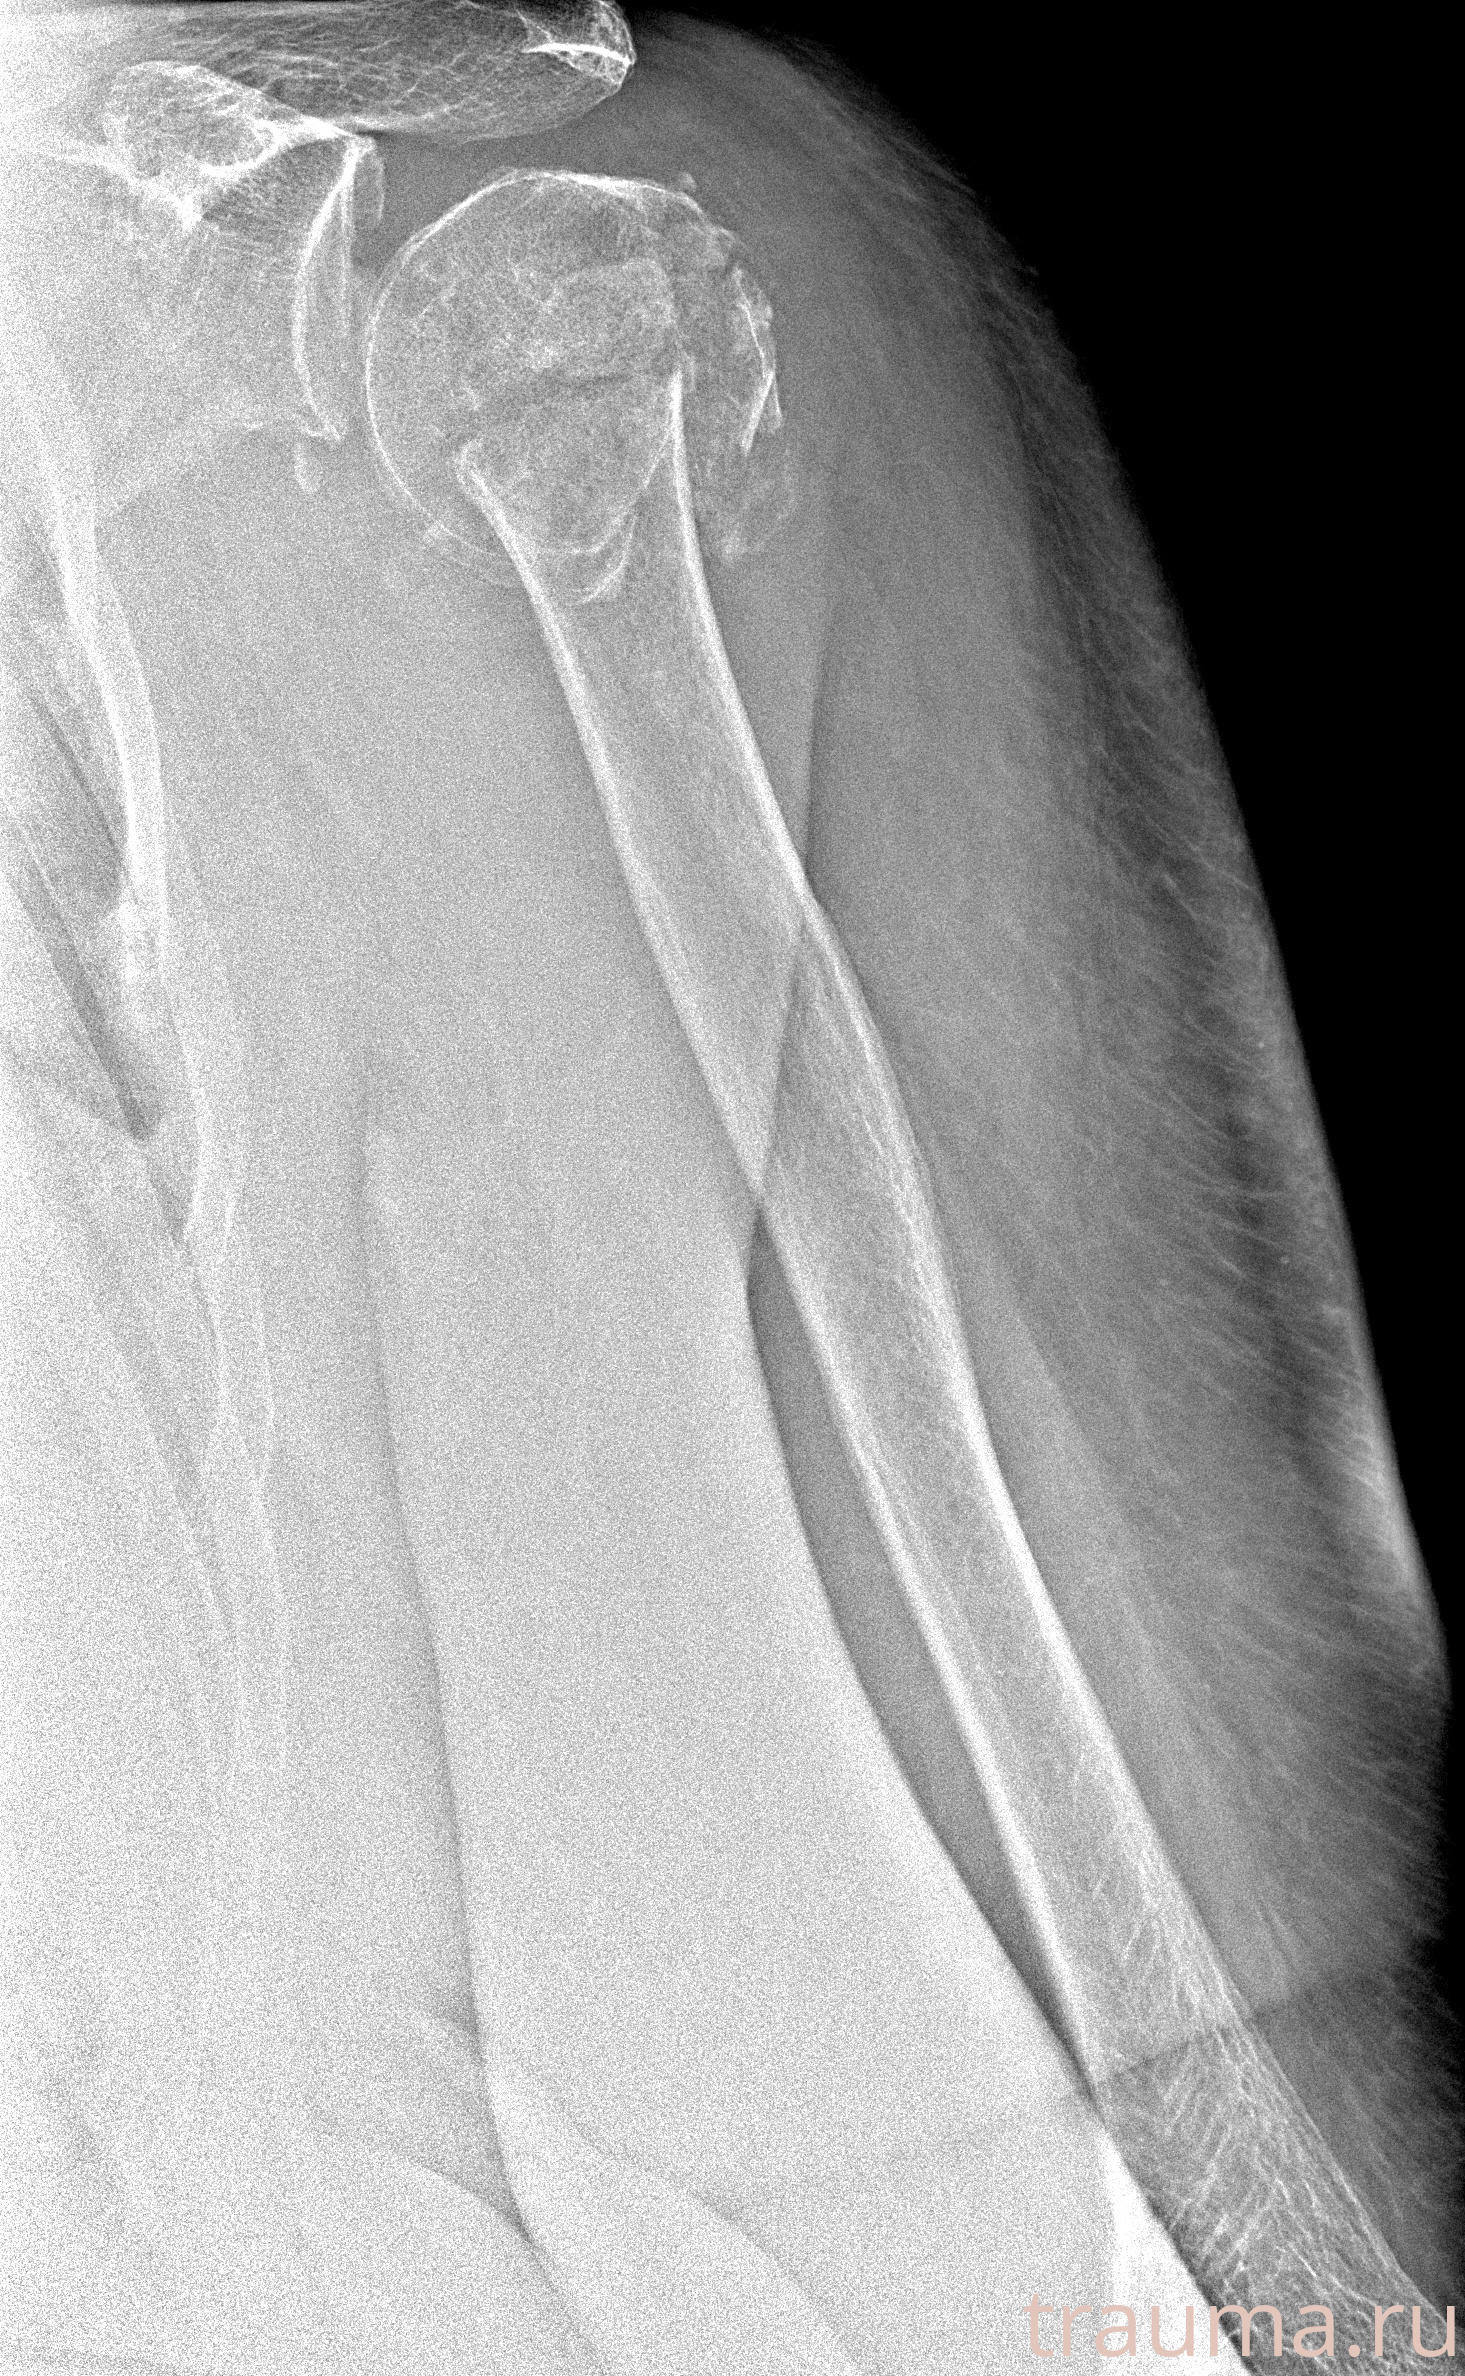

Рентгенограммы

Рентген на дому: по вашему адресу приезжает врач-рентгенолог, травматолог-ортопед с мобильным рентгеновским аппаратом, проводит диагностику травмы или заболевания, делает необходимые рентгенограммы, дает рекомендации по дальнейшему лечению. Получить качественные снимки в домашних условиях возможно благодаря уникальной методике, разработанной МосРентген Центром для института  Склифосовского